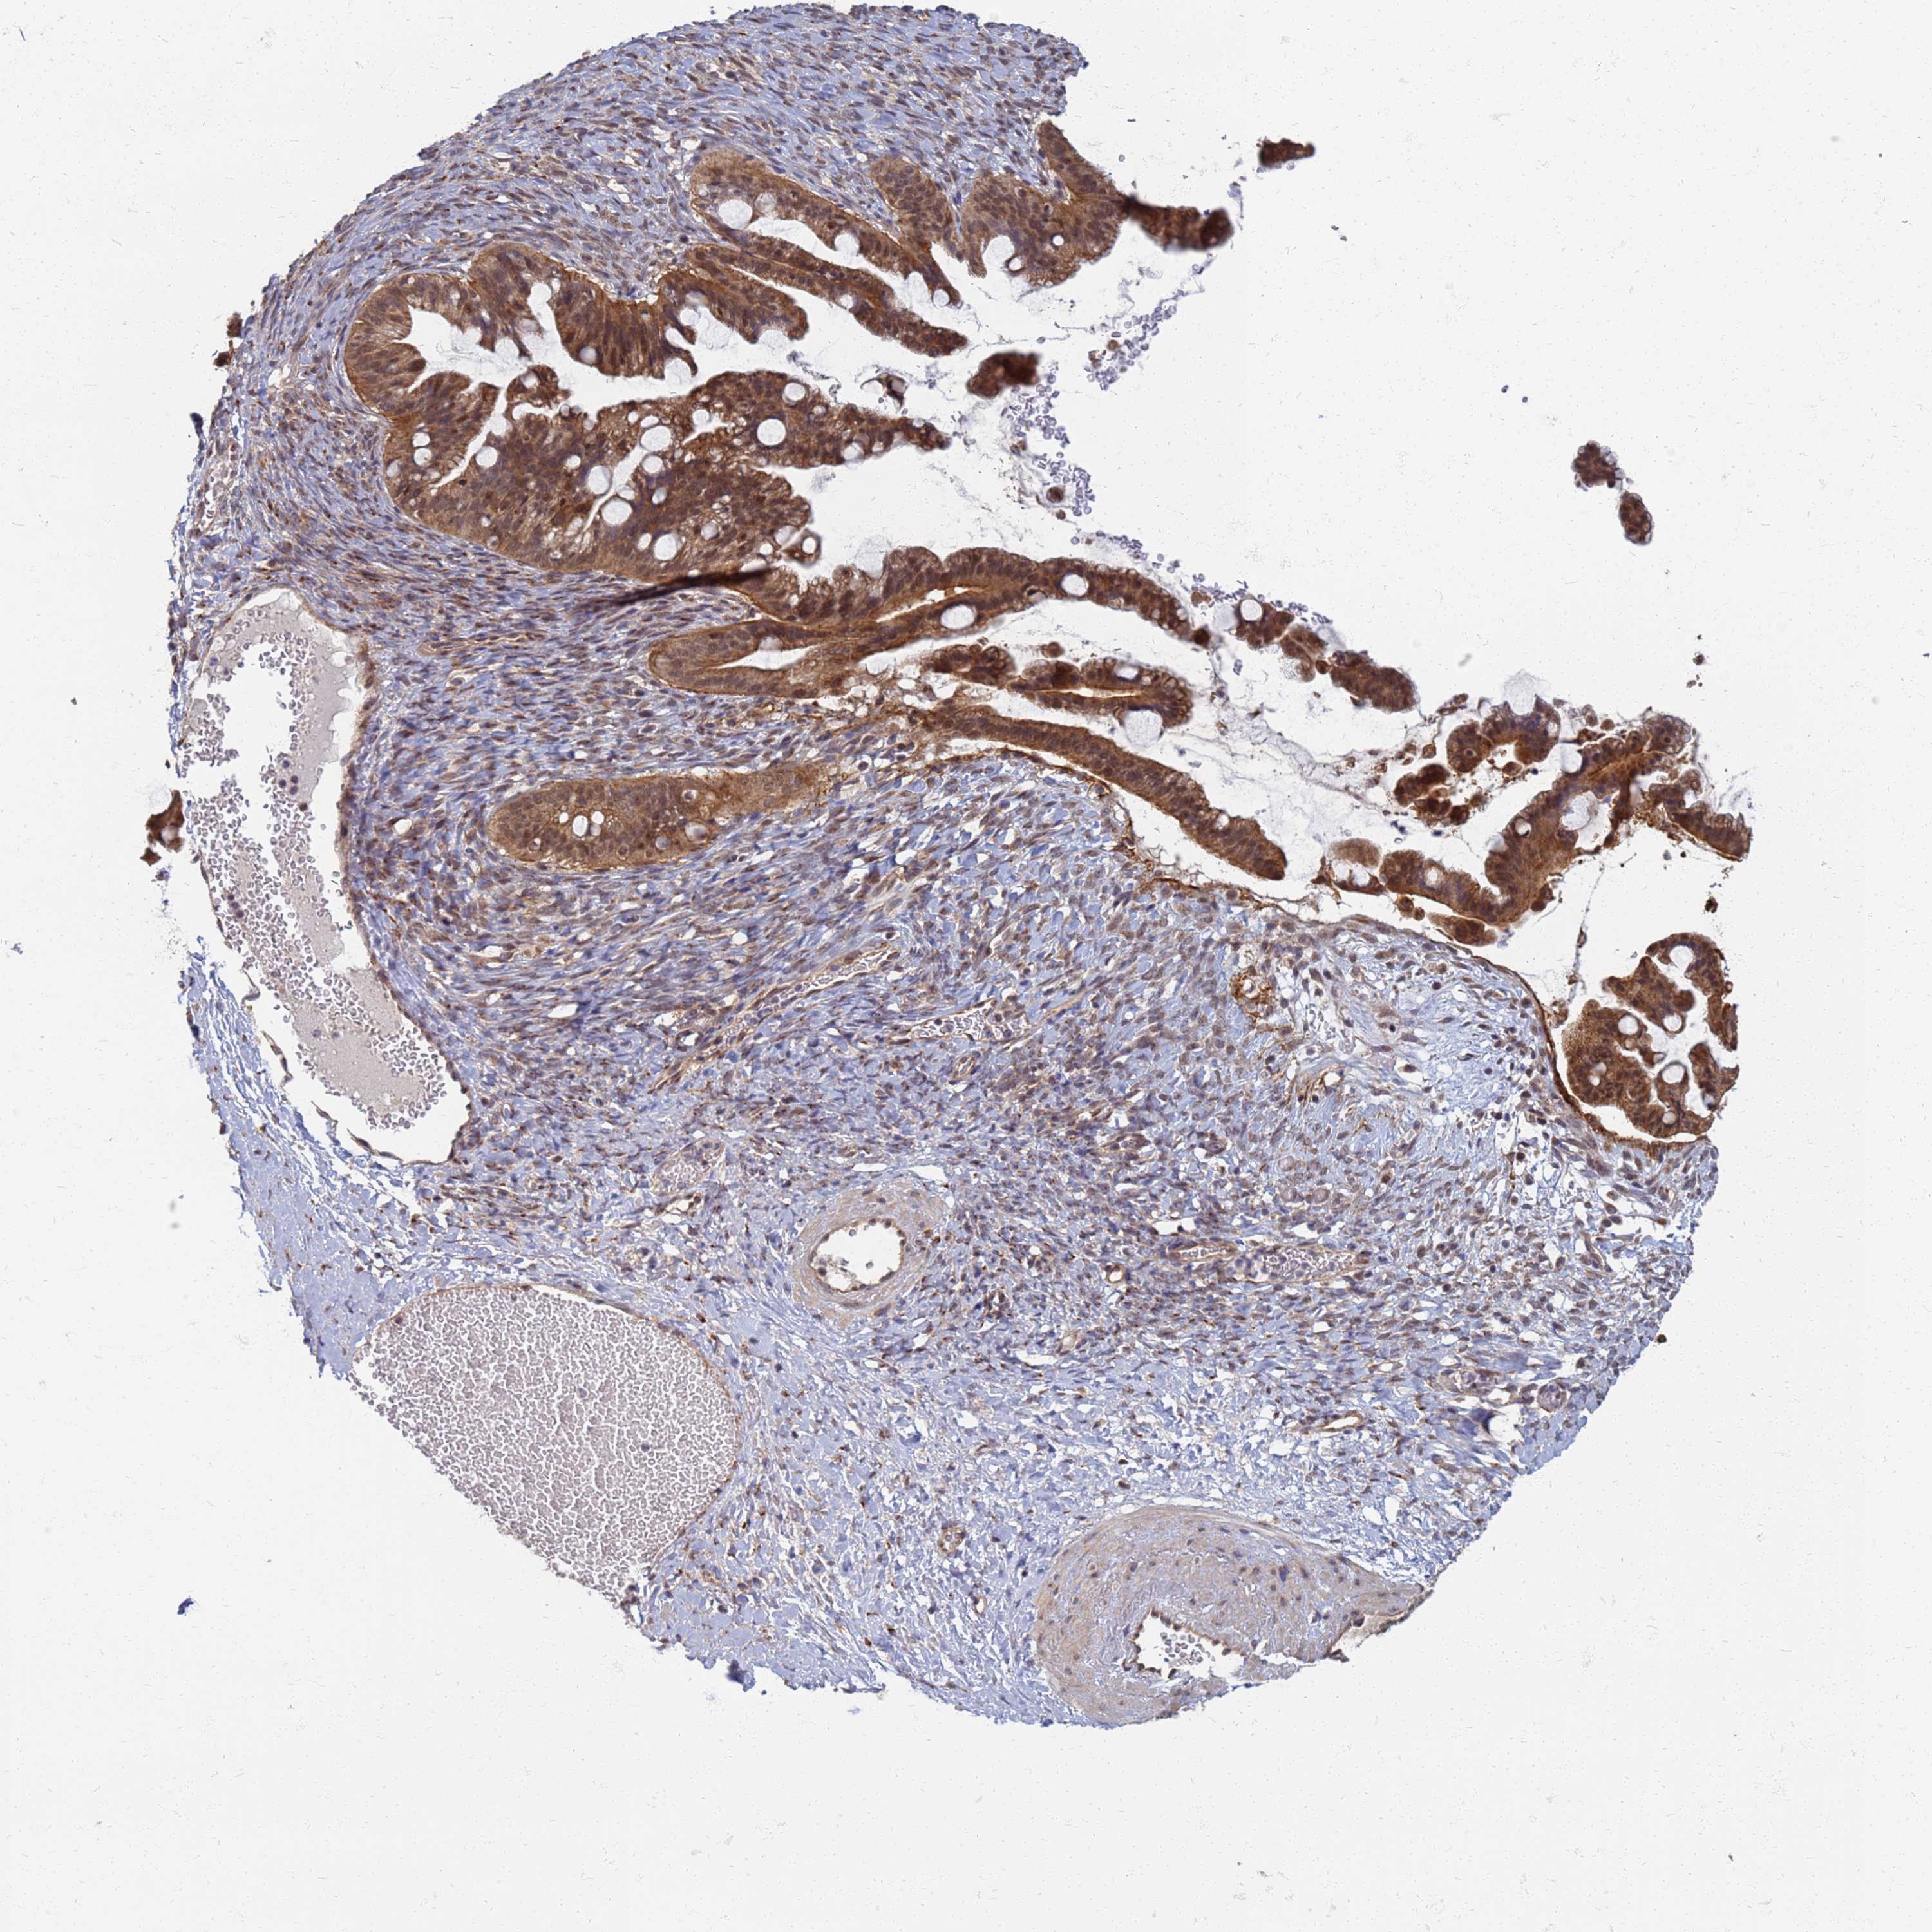

OVARIAN CANCER - Protein expressioni

A mouse-over function shows sample information and annotation data. Click on an image to view it in a full screen mode. Samples can be filtered based on level of antibody staining by selecting one or several of the following categories: high, medium, low and not detected. The assay and annotation is described here.

Note that samples used for immunohistochemistry by the Human Protein Atlas do not correspond to samples in the TCGA dataset.

Antibody stainingi

Antibody staining in the annotated cell types in the current human tissue is reported as not detected, low, medium, or high, based on conventional immunohistochemistry profiling in selected tissues. This score is based on the combination of the staining intensity and fraction of stained cells.

Each image is clickable and will lead to virtual microscopy that enables deeper exploration of all samples and also displays staining intensity scores, fraction scores and subcellular localization as well as patient and tissue information for each sample.

Antibody HPA036348

Antibody HPA036349

Antibody CAB002422

Antibody CAB005258

Cystadenocarcinoma, serous, NOS

Carcinoma, NOS

Cystadenocarcinoma, mucinous, NOS

Carcinoma, endometroid